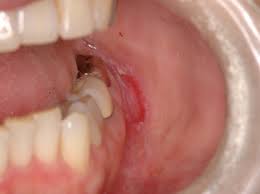

- 입안의 궤양: 2주 이상 지속되는 통증 없는 궤양

- 출혈: 이유 없는 출혈

- 구강 내 혹이나 덩어리: 만져지는 종괴